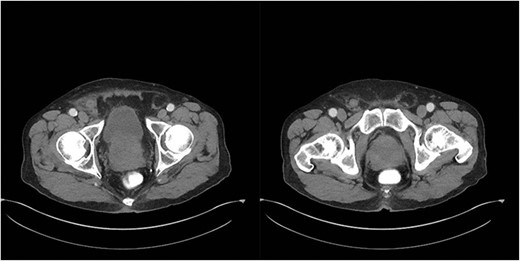

An 81-year-old male with a past medical history of childhood repair of cardiac septal defect presented to our emergency department (ED) with a two-day history of vague abdominal pain that migrated to his right groin with an associated non-reducible right groin mass. The non-reducible groin mass persisted, and his pain progressed that prompted him to come to the ED. Clinical examination revealed a firm, tender and irreducible right inguinal mass. The remaining clinical and laboratory tests were normal. Contrast-enhanced computed tomography (CT) of the abdomen and pelvis was performed. CT presented an acute appendicitis within a right inguinal hernia and a dilated appendix, measuring 13 mm in diameter and demonstrated periappendiceal fat stranding with no evidence of rupture (Figs 1–3). Patients’ history, physical exam and imaging findings were consistent with the preoperative diagnosis of an Amyand’s hernia with acute appendicitis. It was determined the patient will require operative intervention.

Axial CT abdomen with oral contrast showing a dilated appendix periappendiceal fat stranding within a right inguinal hernia and no evidence of rupture.